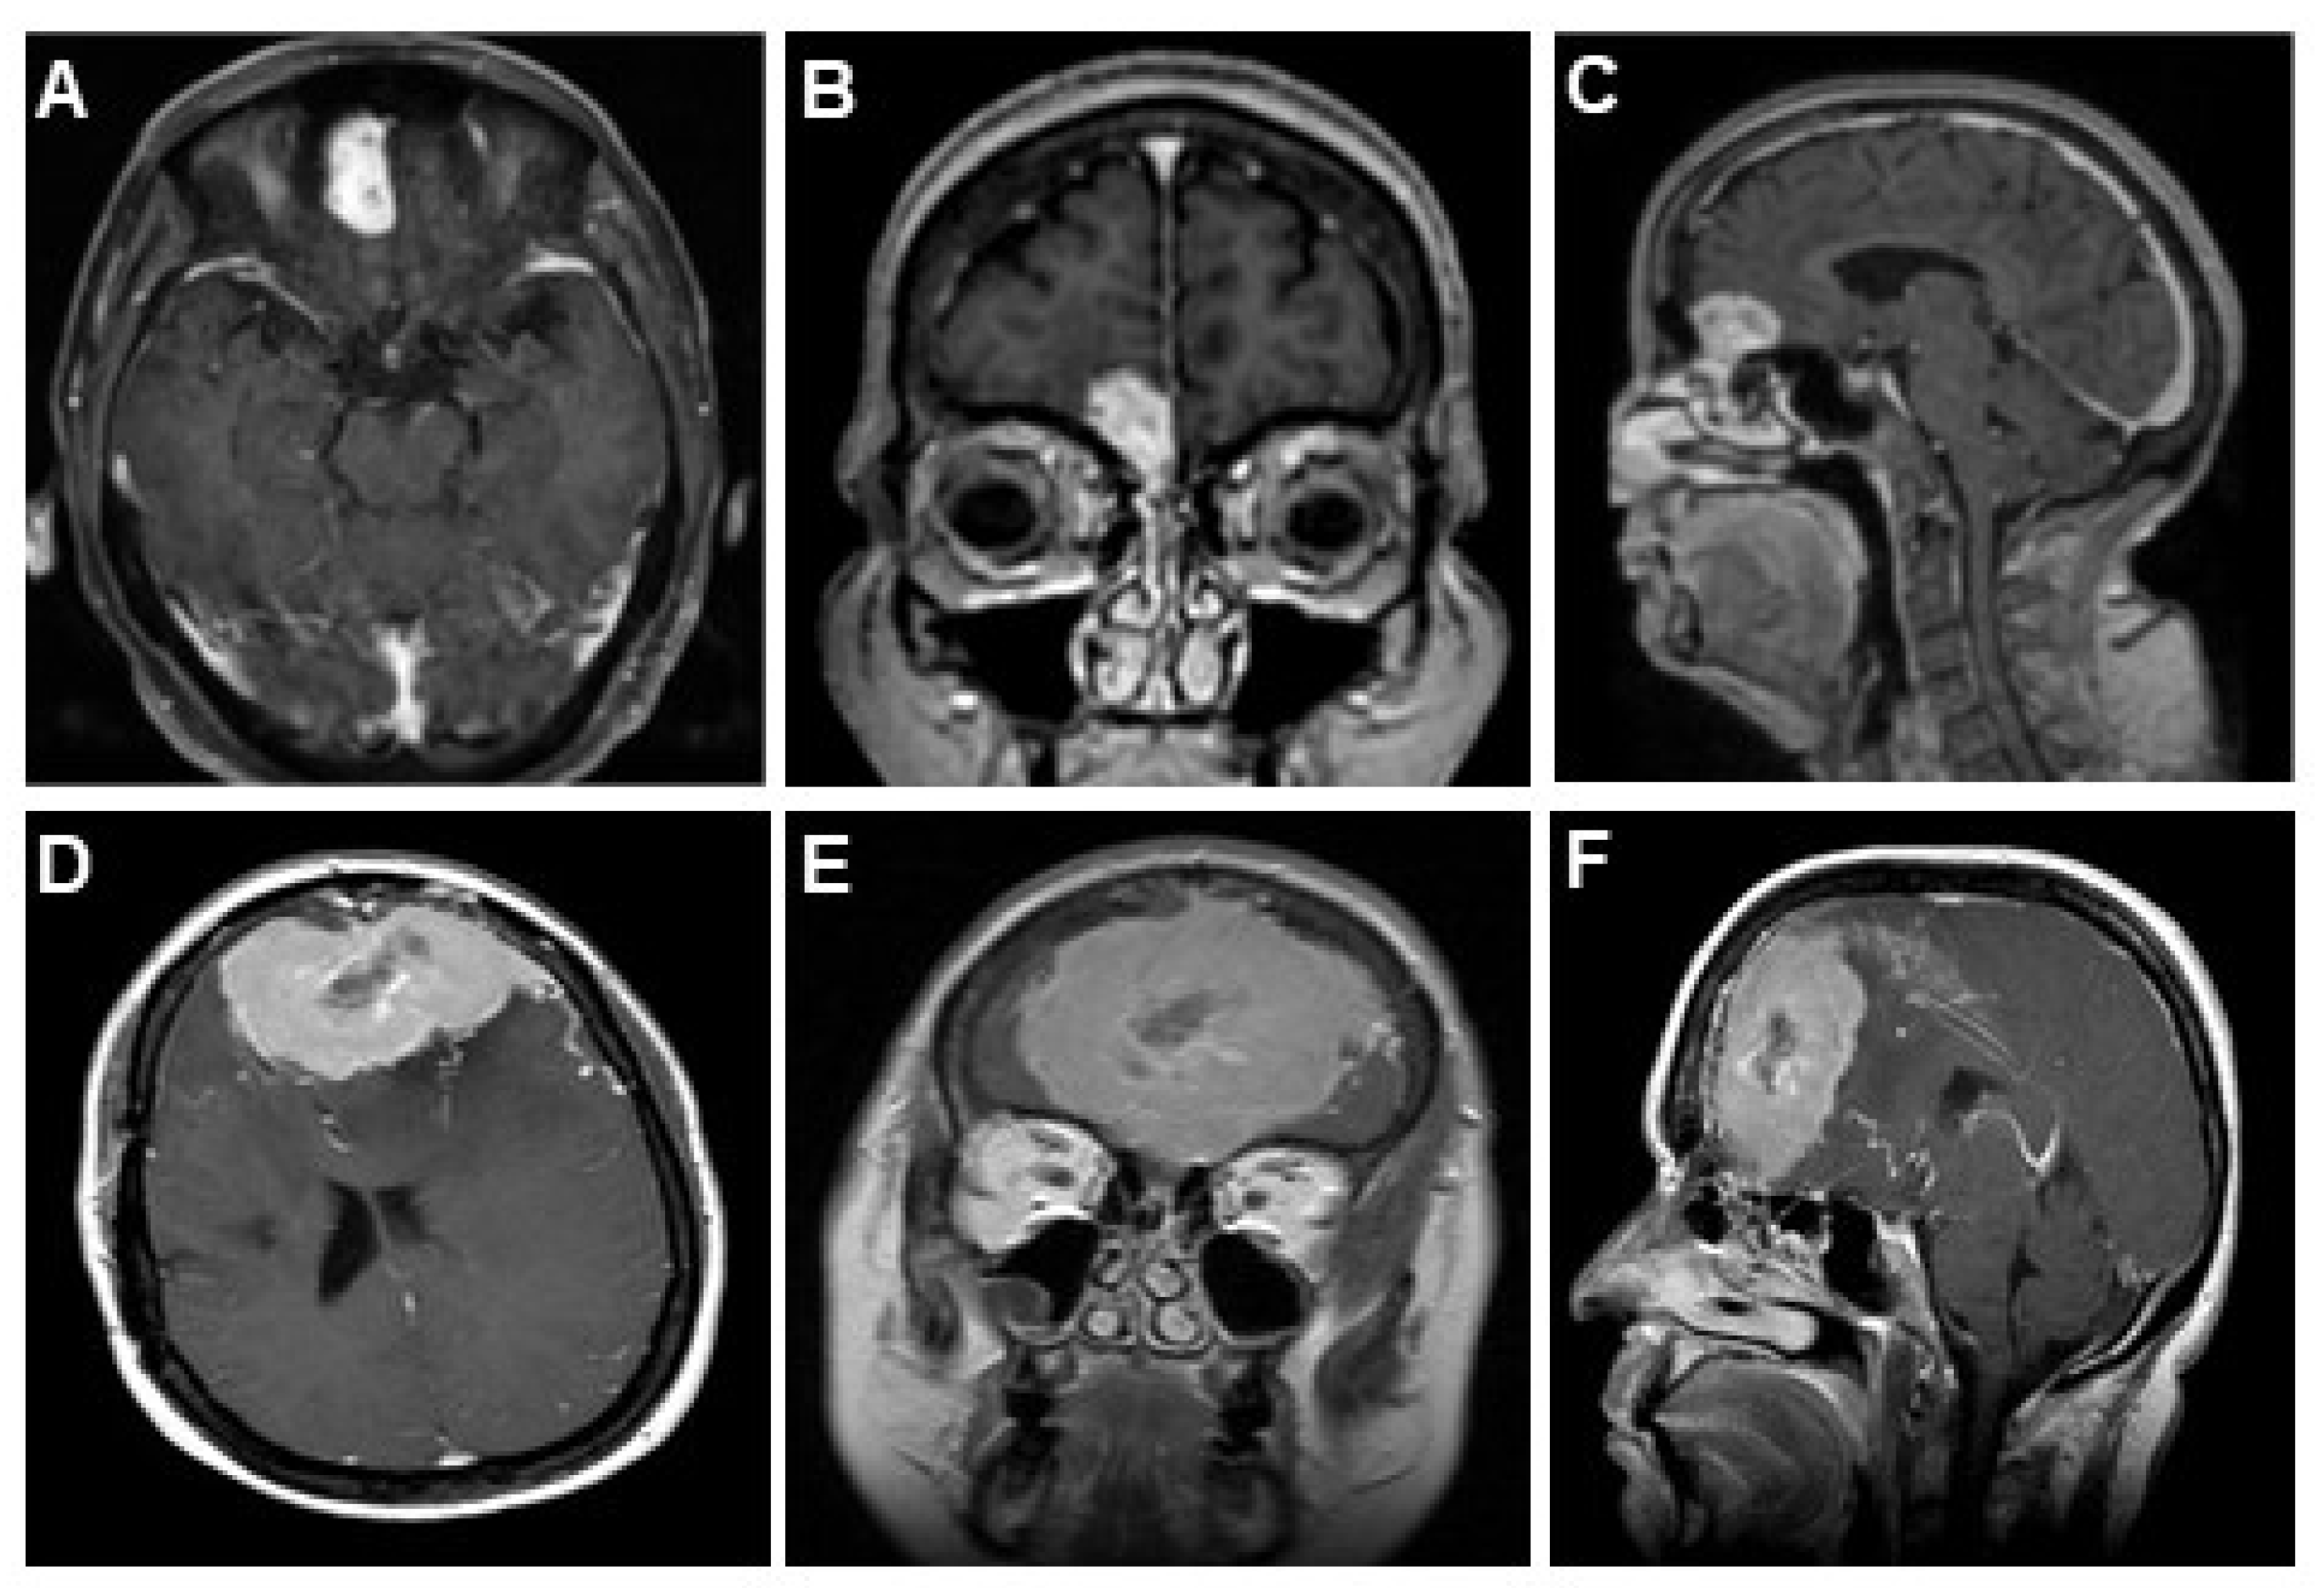

4.1. Presenting Symptoms and Preoperative Radiographic Appearance